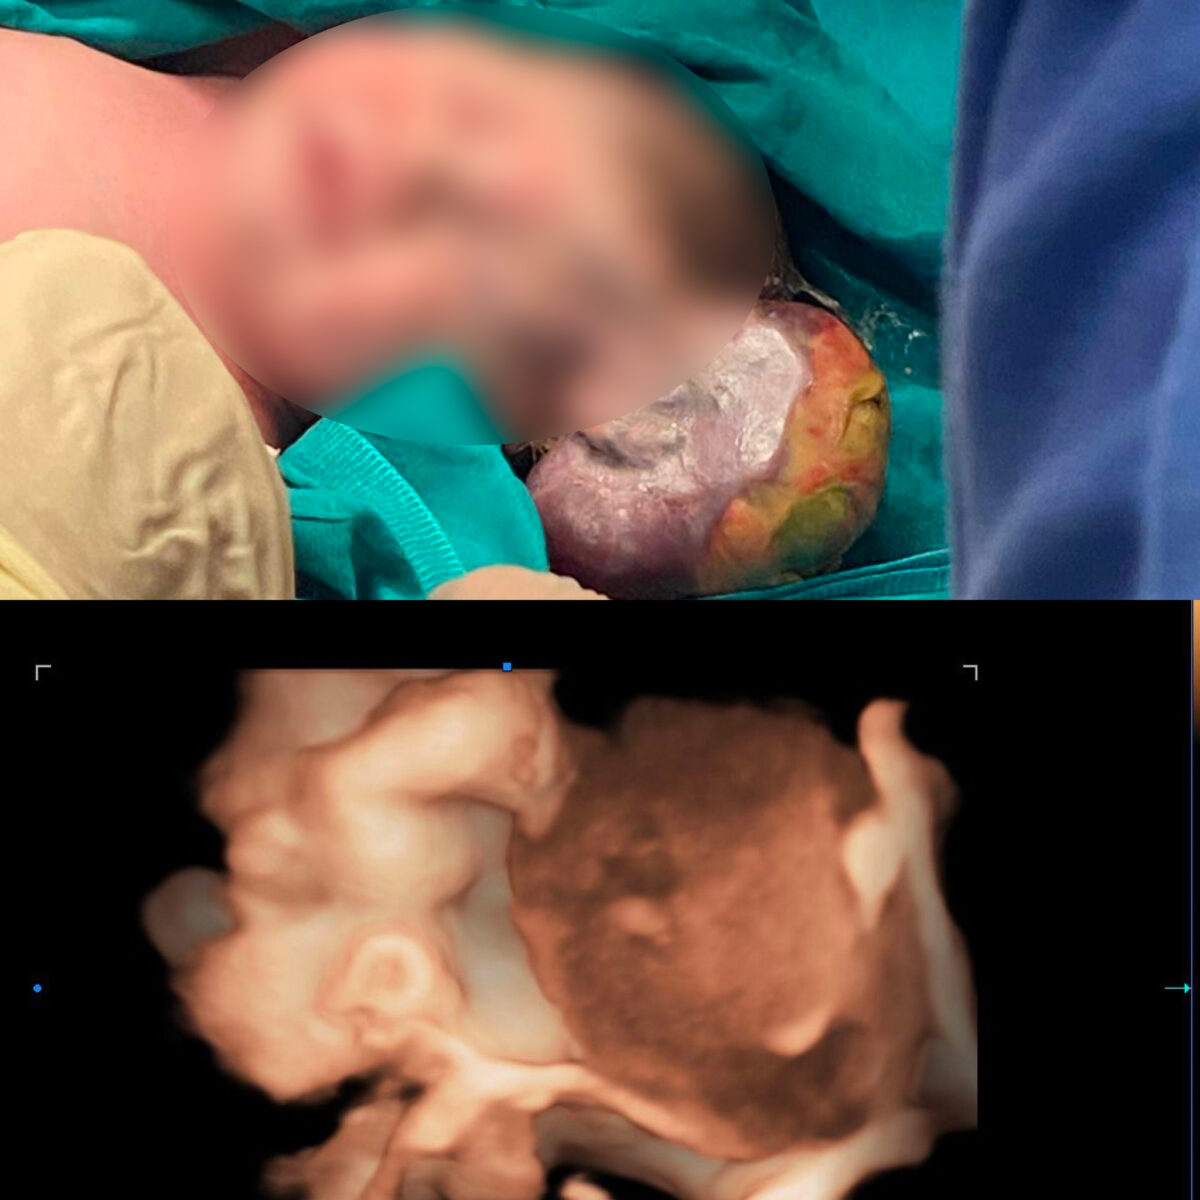

Una massa grande quanto una seconda testa che spunta dalla fronte di una bimba appena nata: le malformazioni neonatali sono eventi drammatici per i neo genitori, ma la medicina oggi può fare la differenza. A dircelo è la storia di Anna (nome di fantasia), una bimba il cui destino è stato cambiato da una diagnosi corretta e da un approccio attento anche all’aspetto psicologico da parte degli specialisti del Policlinico Gemelli di Roma.

L’intervento cui la bimba è stata sottoposta subito dopo la nascita è infatti riuscito “alla perfezione, senza impatto sull’estetica del volto”, dicono dalla struttura. Oggi Anna è una neonata come tutte le altre, senza esiti estetici evidenti.

Come procedere? Successive ecografie hanno permesso di appurare che la formazione partiva dalla parte alta della fronte della neonata. Così l’esperta di medicina fetale Anita Romiti ha utilizzato ecografia 3D e Doppler ad alta sensibilità per caratterizzare al meglio morfologia, sede e vascolarizzazione della malformazione. Una sfida, anche a livello psicologico, per i futuri genitori.

A intervenire, subito dopo la nascita nella sala operatoria della Terapia Intensiva Neonatale, è stato il chirurgo pediatrico Lorenzo Nanni. “La grande massa – spiega – era collegata alla volta cranica della piccola con un peduncolo esteso per circa 7 cm e del diametro di circa un centimetro. Crescendo inoltre, si era parzialmente ripiegata su sé stessa, andando incontro a una parziale ischemia: un dettaglio che ha facilitato la rimozione chirurgica, riducendo il rischio di sanguinamento”, aggiunge il ricercatore di Chirurgia pediatrica e infantile all’Università Cattolica.

Come si è visto dopo l’esame istologico, la malformazione era un miofibroma esofitico di grandi dimensioni, esteso dalla volta cranica alla regione prefrontale. Una lesione importante ma benigna, dunque.